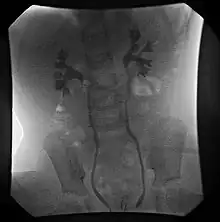

VCUG demonstrating bilateral Grade II (non-dilating) vesicoureteral reflux.

VCUG is the method of choice for grading and initial workup, while RNC is preferred for subsequent evaluations as there is less exposure to radiation. A high index of suspicion should be attached to any case where a child presents with a urinary tract infection, and anatomical causes should be excluded. A VCUG and abdominal ultrasound should be performed in these cases